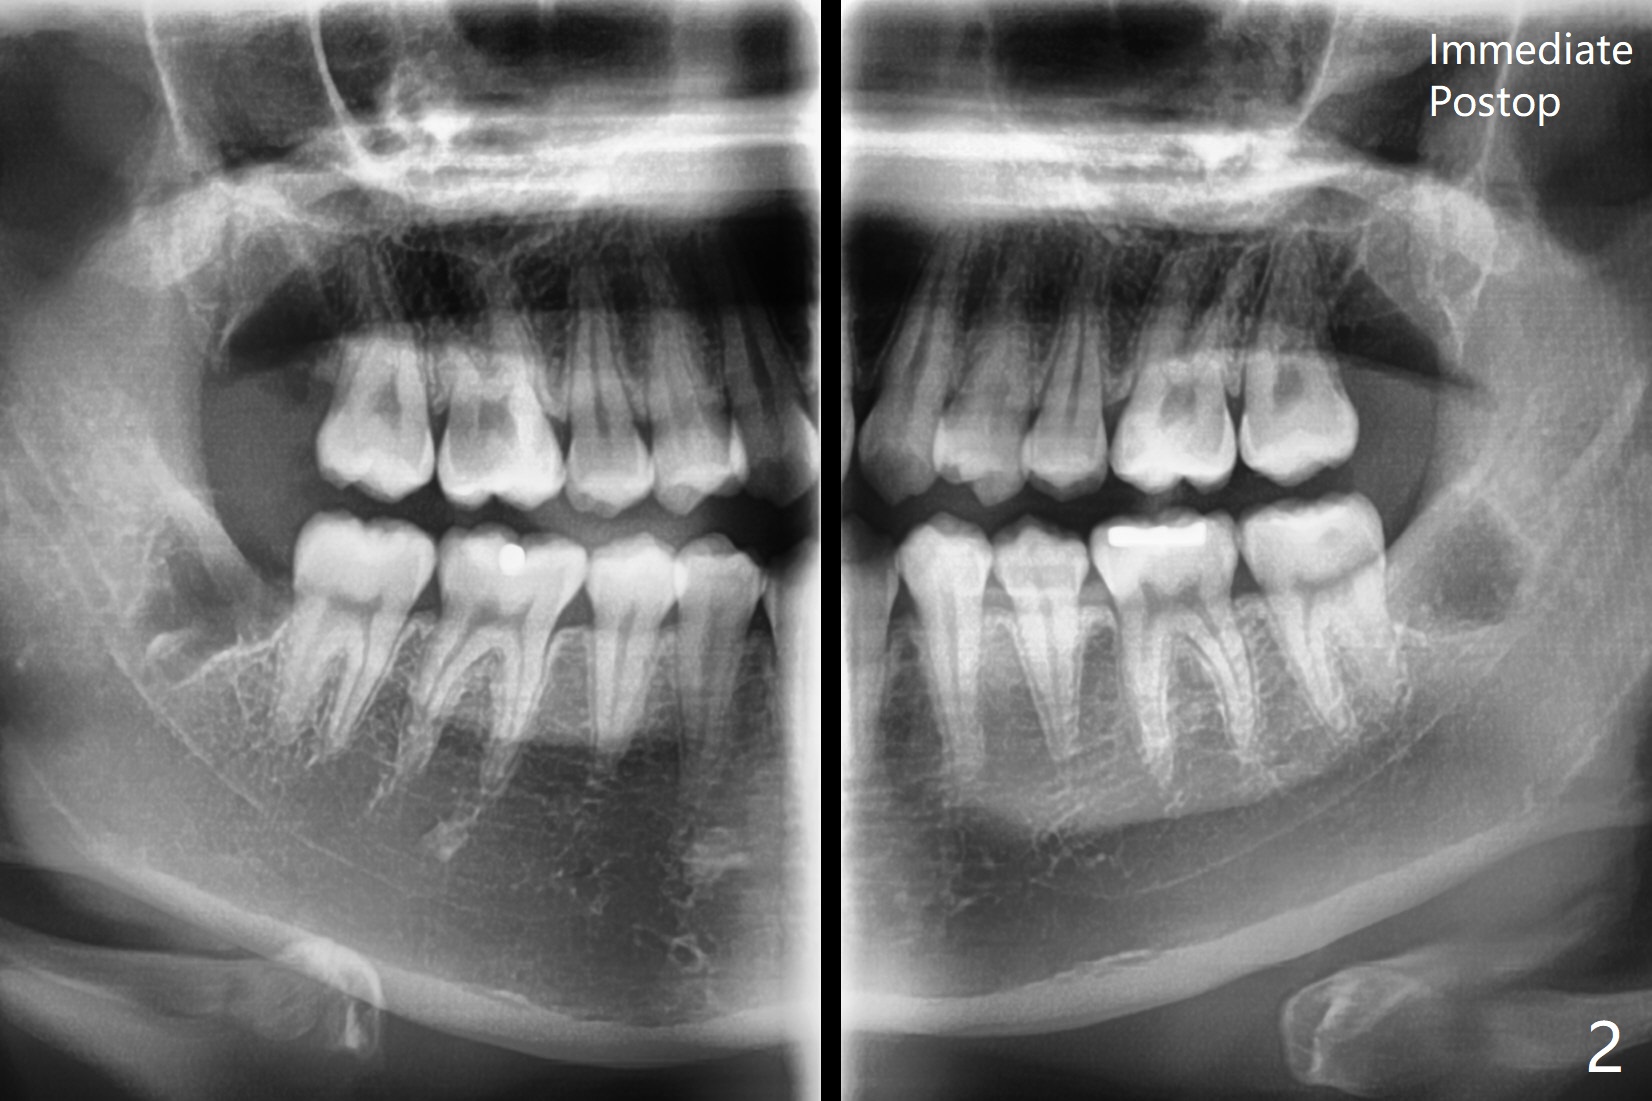

Expect Bone Density Increase in 3-4 Months

A 18-year-old woman with suboptimal oral hygiene had pericoronitis at #1 and 17 (Fig.1). To prevent dry socket, collagen plug is placed at #17 and 32 post extraction (Fig.2). She is uninterested in bone graft, which turns out unnecessary for young patients.